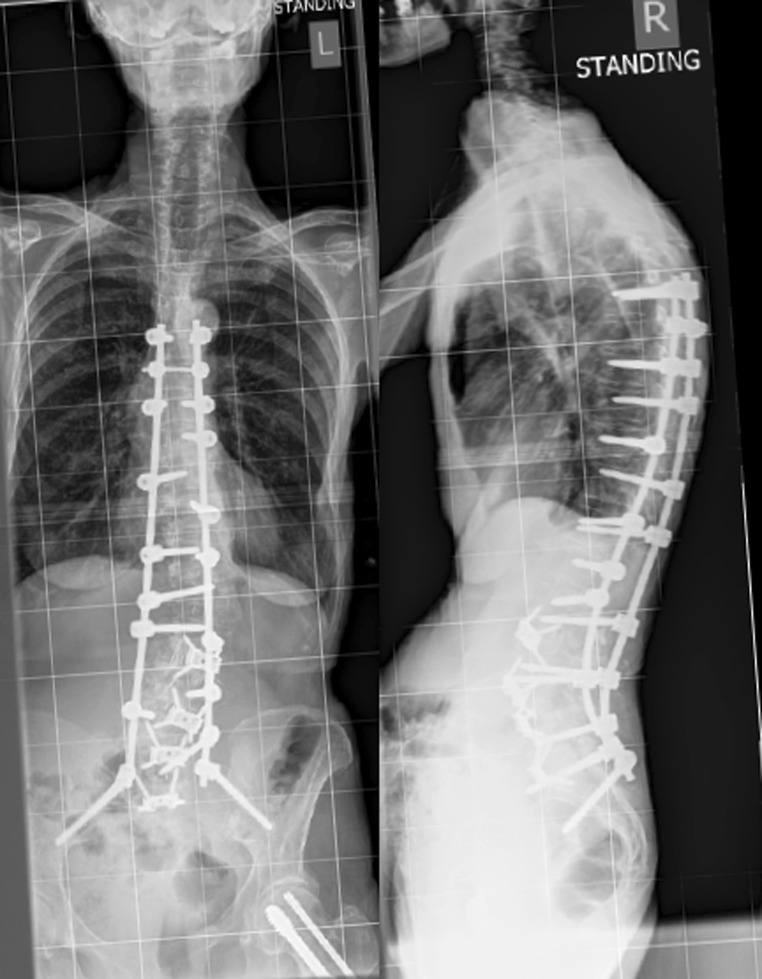

The extensive release resulting from a total discectomy with removal and release of the annulus fibrosus allows for more restoration of lordosis [3] in the respective segment with better support due to the ability to insert a larger cage compared to the posterior access. This makes anterior access to the lumbar spine interesting for adult deformity correction, particularly restoration of the sagittal profile as illustrated in Fig. 1. Furthermore, anterior lumbar interbody fusion has been widely used to support the caudal ends of long spinal deformity constructs [4] as they are prone to non-union and 360° fusions offer higher union rates [5].

Fig. 1.

This shows an example of four-level ALIF and second-stage posterior instrumentation for a sagittal deformity. The restoration of lumbar lordosis was largely achieved by anterior release and cage placement